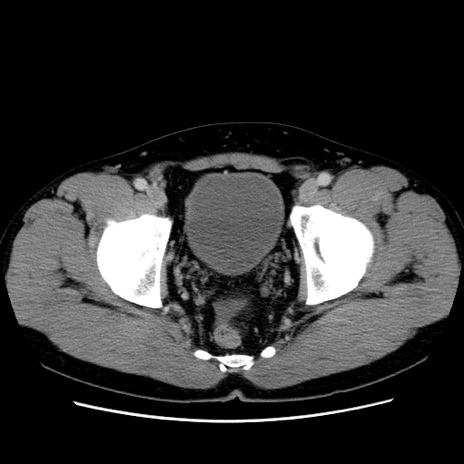

症例4(横断像)

【症例】30歳代男性

【主訴】腹痛、嘔吐

【現病歴】昨晩から突然の腹痛あり、その後嘔吐、軟便も出現。腹痛が改善しないため救急搬送となる。2日前にしめ鯖の食事歴あり。

【身体所見】意識清明、苦悶様、BP 135/90mmHg、BT 35.7℃、腹部:平坦、やや硬、心窩部〜臍部に自発痛、圧痛あり、筋性防御+、反跳痛-

【データ】WBC 8100、CRP 0.57